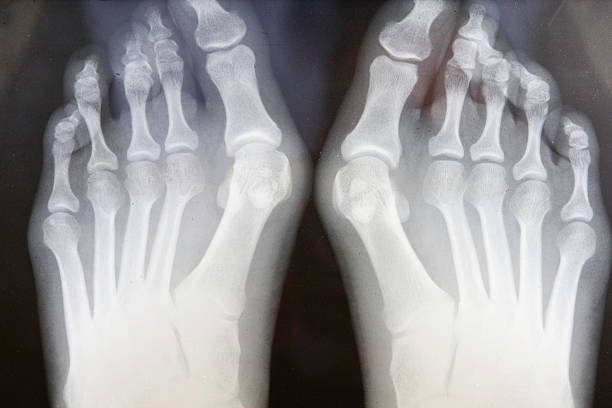

무지외반증이란 엄지발가락이 새끼발가락 쪽으로 휘어지고, 중족골 관절은 바깥쪽으로 튀어나오는변형을 일으키는 질환입니다.

치료 방법은 hallux valgus angle 에 따라 달라질 수 있습니다. 초기 20도 미만인 경우, 당장 수술할 수 없는 소아 청소년과 임산부의 경우 교정기를 통해 수술을 지연할 수는 있습니다. 그러나 교정이 치료의 방법은 아니며, 단지 변형을 늦춰 주는 보존적 치료라고 합니다.

기존의 개방적인 수술의 뼈를 깎아 봉합하는 방식과 달리 현재는 hallux valgus angle가 보편화되어 이에 따라서 병기를 구분하고 수술의 방법을 적용할 수 있는 선별적인 방식이 적용되고 있다고 합니다.

20~25도 미만의 병기에는 미세 침습방식의 (MIS) 교정술을 적용해 볼 수 있다고 합니다. 엄지발가락 주변에 2~3개의 미세한 구멍을 이용해 수술하는 방법입니다. 피부를 봉합하거나 할 필요가 없어 미용과 흉터에 대한 부담이 적고 덜 아프고 회복이 빠른 것이 장점입니다. (구멍을 뚫고 엄지 뼈를 안쪽으로 들여서 1자로 정렬을 맞춘다고 합니다. )

다음은 양측 발병 및 25도 이상의 육안으로도 확인 가능한 경우의 변형입니다. 이런 경우 단일 절개 복합 교정술을 시행한다고 합니다. 기존 절골 교정술은 두 번의 개방에 비해 휘어진 뼈에 미세한 실금을 내어 내측으로 잡아당겨 정렬을 맞추는 수술입니다. 기존 고식적 수술이 두 번의 절개와, 뼈를 깎는 수술로 통증이 무척 컸던 반면에 교정술은 실금을 내서 정렬을 하기 때문에 통증이 상대적으로 덜 하여 양측 수술도 가능하다고 합니다.